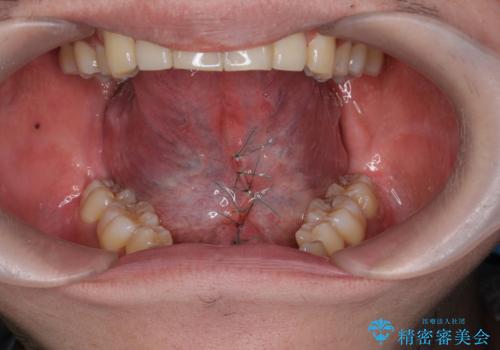

舌小帯の形成で達成する滑舌の改善

- 長年、指摘され悩みの種であった滑舌の改善を希望され来院されました。

舌の動きを制限してしまう下部のヒダが長い状態を改善する、舌小帯の形成を即日で行い滑舌の改善を計画します。

舌小帯の形成は10分程度で終わる小手術です。

手術を受ける前は怖かったけれど、長年悩みの種であった滑舌が改善できたと喜んでいただくことができました。